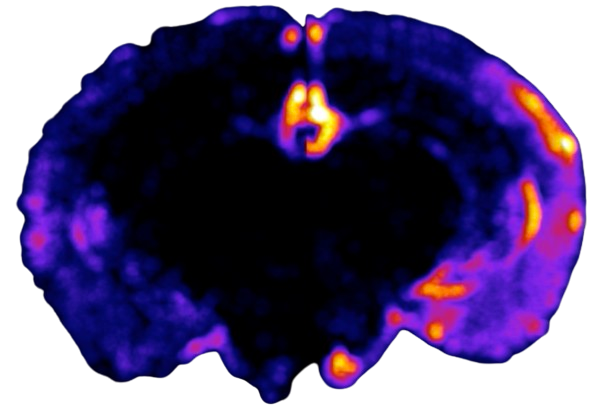

Animals rely on sounds for survival, and social/reproductive interactions. Our brain must perform the challenging tasks of rapidly recognizing, categorizing, and assigning communicative importance to sounds in a noisy environment. The instructions to these functions are found in the precise connections neurons make with one another. We study evolutionarily conserved mechanisms for decoding social calls in the Auditory Cortex of rodents. The organization of the cerebral cortex may appear stereotyped, but new tools that allow detailed investigation of neural circuits have revealed significant differences between cortical areas that perform different functions. These circuit specializations embedded in stereotyped modules are now believed to be the secret ingredients that enable cortical areas to perform specific tasks. Our goal is to reveal these unique circuit features in the Auditory Cortex and determine their behavioral significance.